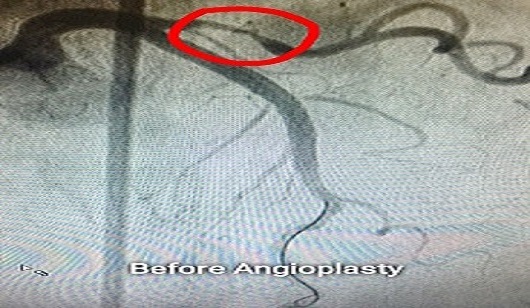

Angiography showed critical lesion in LAD and Diagonal vessel. It is called as BIFURCATION lesion. Medina 1,1,1. Lesion. This complex and technically challenging. Angioplasty was done by Dr. Sachin Patil by MINI-CRUSH technique. He used 2 stent strategy and handled the case. She is under regular follow up from last 5 yrs and is doing well.